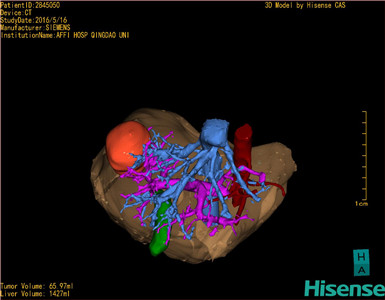

通过调节窗宽窗位调整CT序号,对肿瘤,肝实质,胆囊,下腔静脉,肿瘤,肝动脉、门静脉及肝静脉等进行三维重建;系统自动计算肿瘤体积和肝脏体积。

模拟手术操作,自动计算切除肿瘤体积。肝脏体积为1427ml,肿瘤体积为65.97ml,肿瘤体积为肝脏体积的4.6%,通过比对40-50岁正常肝脏体积为1368.38±279.24ml,通过术前模拟手术,精准判断切除后剩余肝脏体积能耐受,避免肝衰竭发生。

术前手术方案的规划。

术前三维重建:

重建图片